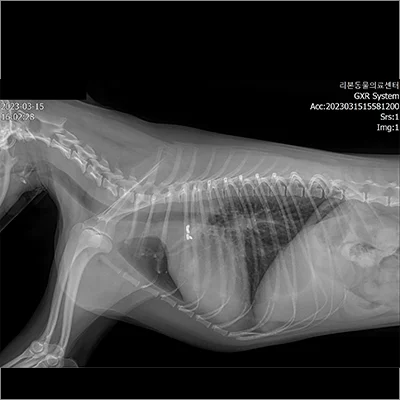

PDA 전

PDA 후

폐엽절제 전

폐엽절제 후